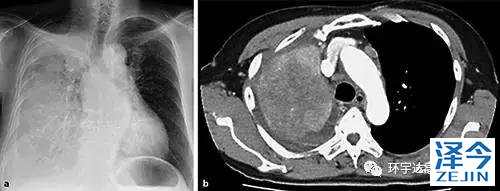

图1a显示右肺渗透性降低的胸片。b胸部的CT图像显示右肺和右胸腔积液中的巨大肿块

肺腺癌患者服用靶向药物后出现耐药,检测后竟发现转为小细胞癌!为什么会出现这种情况,肿瘤患者靶向治疗耐药后应该怎么办?六十五岁女士由于右胸痛及劳累性呼吸困难而来医院检查。CT扫描显示右上叶和右胸腔积液中有巨大肿块(图1 b)。另外,左肺,肝,左肾上腺以及纵隔淋巴结肿大也发现多个肿块。